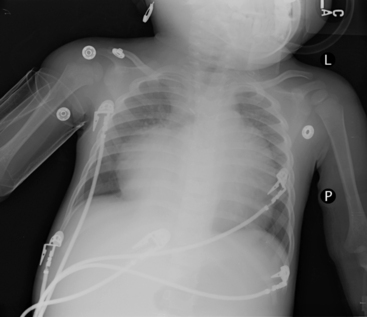

The alignment and the position of the patient at the time the film is taken also must be considered (Fig. 10-1). To determine whether a patient was positioned appropriately during the radiograph exposure, several structures should be evaluated. This evaluation includes the position of the trachea, curvature of the spine, position of the clavicles, length and symmetry of the ribs, and cardiac landmarks. If the patient is positioned straight and not rotated on the image, the trachea should project in the midline within the upper third of the chest. The spine should be straight with the intervertebral bodies outlined as separate from the disc spaces. With good alignment, the clavicles are of equal size and length. The medial ends of the clavicles should be equidistant from the thoracic spinous processes; they are normally projected over the lung apices and overlap the anterior first ribs. If the clavicles both appear horizontal and of equal size and length, a true AP or PA view was obtained.14 If, on the other hand, one clavicle appears to be smaller than the other (because it was farther away from the x-ray tube at the time the film was taken), or if one clavicle is at a different angle than the other, the patient was probably rotated, and an oblique view of chest structures appears on the radiograph, creating the appearance that one side of the chest image (and one clavicle) is larger than the other. As noted previously, if the apices of the lungs are not visible above the clavicles on an AP or a PA chest film, a lordotic view has been obtained.17

image

Fig. 10-1 In this chest radiograph the child is rotated to the left. Compared with Fig. 10-2, A, which demonstrates evidence of proper positioning, in this film the proximal ends of the clavicles are not symmetrical in appearance. The patient’s left clavicle appears larger. The ribs on the patient’s right side are more curved posteriorly, and ribs in the patient’s left chest are more elongated with greater visualization of the anterior ribs. The cardiac silhouette is more prominent in the left chest with a normal cardiothoracic ratio, but the heart shape is altered by the rotated view.

It is important to consider patient alignment when making any observations about heart size. If the patient is rotated, the oblique image changes the heart shape and distorts the image, causing a spurious increase in cardiac size.